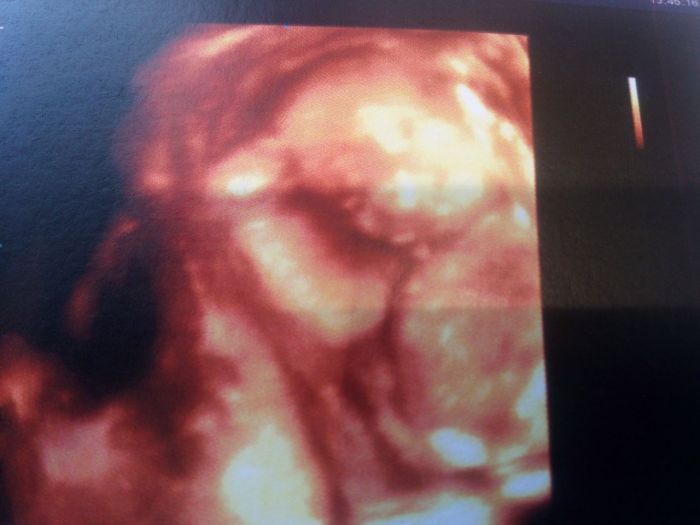

[691284] proc zaspala Jenni?? Nevim jak ktery mudr ale mi chteli 3D uz davno a doktorka nam rekla ze po 24 tydnu to je mnohem lepsi ze mimi chyta vic tuku a nevypada tolik jak ufoun :-D nevim kolik stoji v cr ale tady 80 eur, tak pujdeme jen jednou, jdeme pristi tyden a to budu 29 tyden...

Kdyz jsme se na to ptali, tak jsem byla tusim 16 tyden a udelala nam teda takovou rychlofotecku aby jsme to videli jak to vypada... Neni to moc dobre videt ale mrkni na foto... Jo a Marti me taky hodne lidi tvrdi ze uz mimi ma tvaricku podle rodicu, takze podoba jooo....

[691411]ja právě byla na 3D ve 3O týdnu a říkají,že malinká ma pusinku po mě a nos po tatkovi,tak se právě ptám jestli to je vůbec možný aby už takhle byla někomu podobná :)

[691821]já se právě jenom ptám je krásná :) taky jsem si to řikala,že je vlastně už uplně hotová a že teď jen poroste. Jen jsem chtěla vědět jestli má někdo zkušenosti s 3D a jestli je to možné takhle poznat nic víc